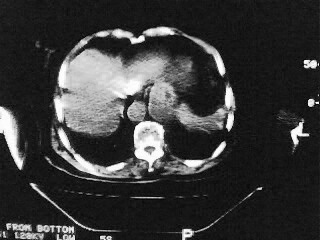

女,79,咳 嗽月余,无其它不适

1)两肺炎症。2)食管裂孔疝可能;建议行上消化道钡餐检查。

(1)食管裂孔疝(2)贲门失弛缓症。建议行上消化道钡餐检查。

后纵隔内左心房至肝左叶后方椎体中线偏左巨大软组织包块,其壁均匀比较薄,其内可见宽气液平。

考虑食管裂孔疝。建议钡餐检查